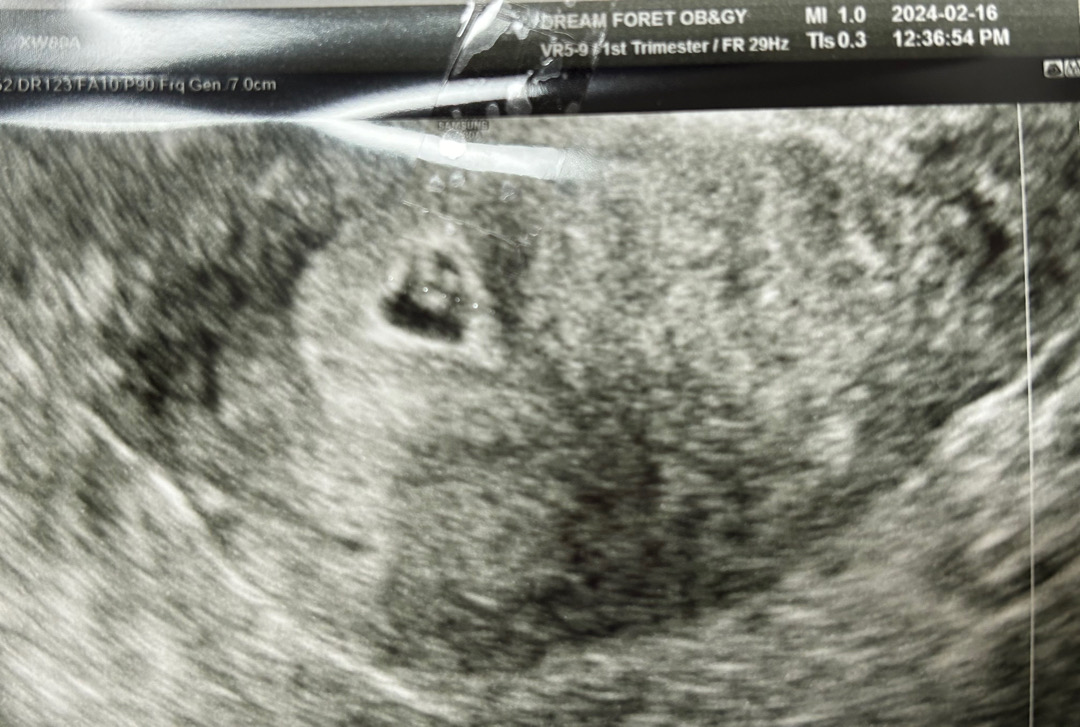

드디어 병원 다녀왔습니다

사실 아직도 임신 한게 믿겨지진 않아요 사실 작년 10월달 제 생일날 유산 되어 좀 힘들다가 금방 털어내고 다시 현생을 지내다 완전 극초기에 뭔가 쎄하여 임테기 하니 다시 두줄 떠서 바로 남편에게 알리고 아직 부모님들에겐 말 안하고 임테기 하면서 조금씩 상황보다가 주기도 모르겠고 이래서 결국 병원 다녀왔네요 ! 다음주에 잘하면 심장소리 듣는데 심장 소리 듣고 임밍아웃하려구요ㅜ!! 아 맞다 병원 가니 4-5주 예상이라고 하셨는데 증상이 진짜 1도 없어요 이런분들 계신가요 ..? 뭐 가슴 통증 살짝 ..??? 입덧 증세도 없고 그냥 그저 배고플뿐이고 .. 이게 맞는건지 ㅜㅜ